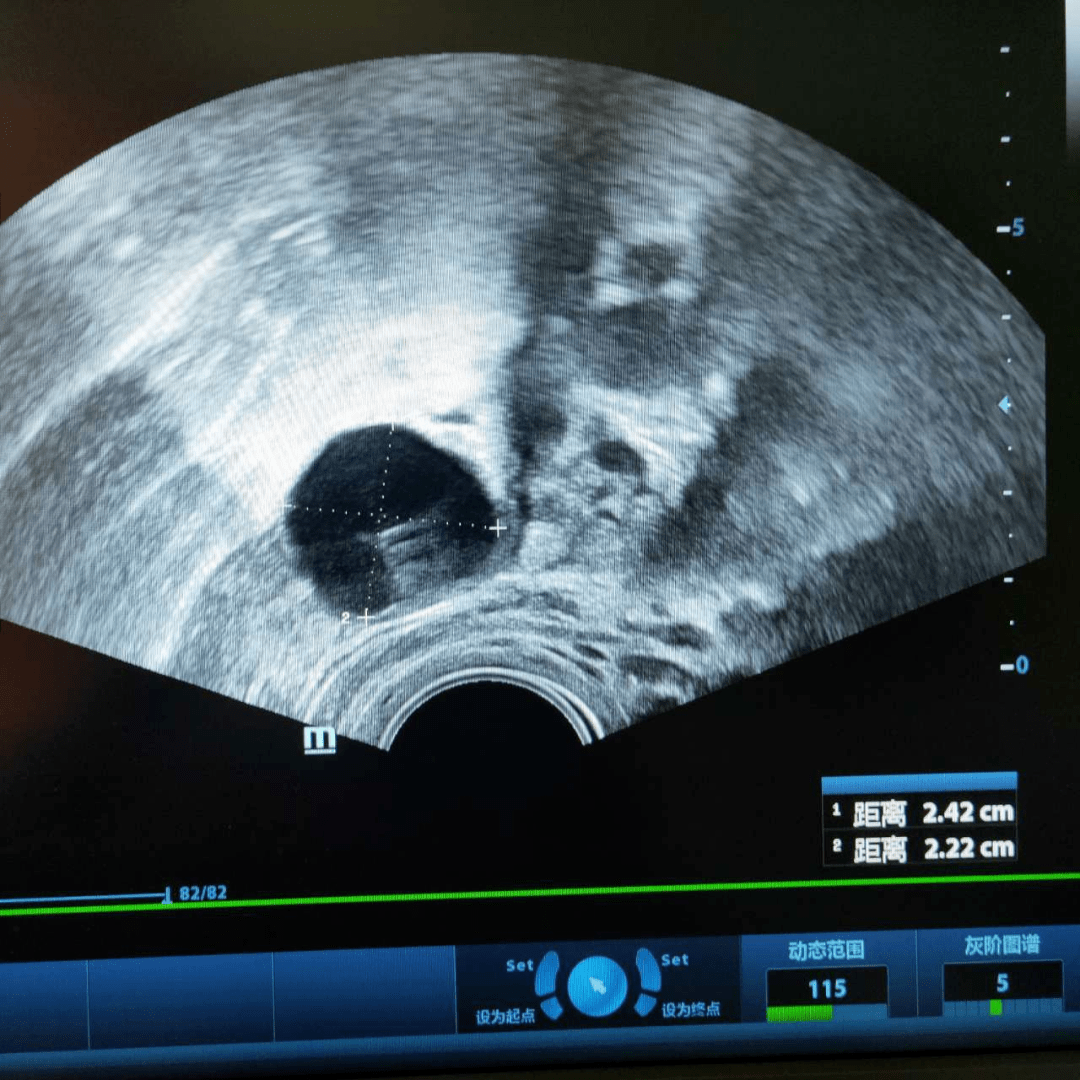

③ b超检测排卵.该方法最准确最有效,是医生推荐的测排卵首选.